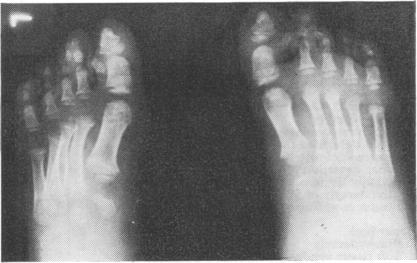

A 5-year-old boy and his father with Pfeiffer syndrome are described. They had acrocephaly, hypertelorism, antimongoloid slant of the palpebral fissures, protrusion of the eyes, large and broad nose, small mandible, irregularly placed teeth, additional upper canine, high-arched palate, partial syndactyly of fingers and toes, brachydactyly of toes, valgus deformity of hypertrophied triangular great toes, broad phalanges of the great toes and broad first metatarsals, accessory epiphyses lateral to the interphalangeal joint of the great toes, and normal intelligence. To our knowledge, this is the first family in which the syndrome is almost totally confined to the head and feet--it spares the upper limbs except for partial skin syndactyly between the fingers--and the third family showing inheritance through three successive generations suggesting an autosomal dominant mode of inheritance. The published papers are reviewed and the clinical and x-ray signs are tabulated.

本文描述了一名患有 Pfeiffer 综合征的 5 岁男孩及其父亲。他们有尖头畸形、眼距过宽、睑裂反蒙古样倾斜、眼球突出、大而宽的鼻子、小下颌、牙齿排列不规则、额外的上尖牙、高拱腭、手指和脚趾部分并指(趾)、脚趾短指畸形、肥大的三角形拇趾外翻畸形、拇趾宽趾骨和宽第一跖骨、拇趾指间关节外侧的副骨骺,且智力正常。据我们所知,这是第一个该综合征几乎完全局限于头部和足部的家系——除手指间部分皮肤并指外,上肢未受累——也是第三个显示连续三代遗传的家系,提示为常染色体显性遗传模式。对已发表的论文进行了综述,并将临床和 X 线征象制成表格。